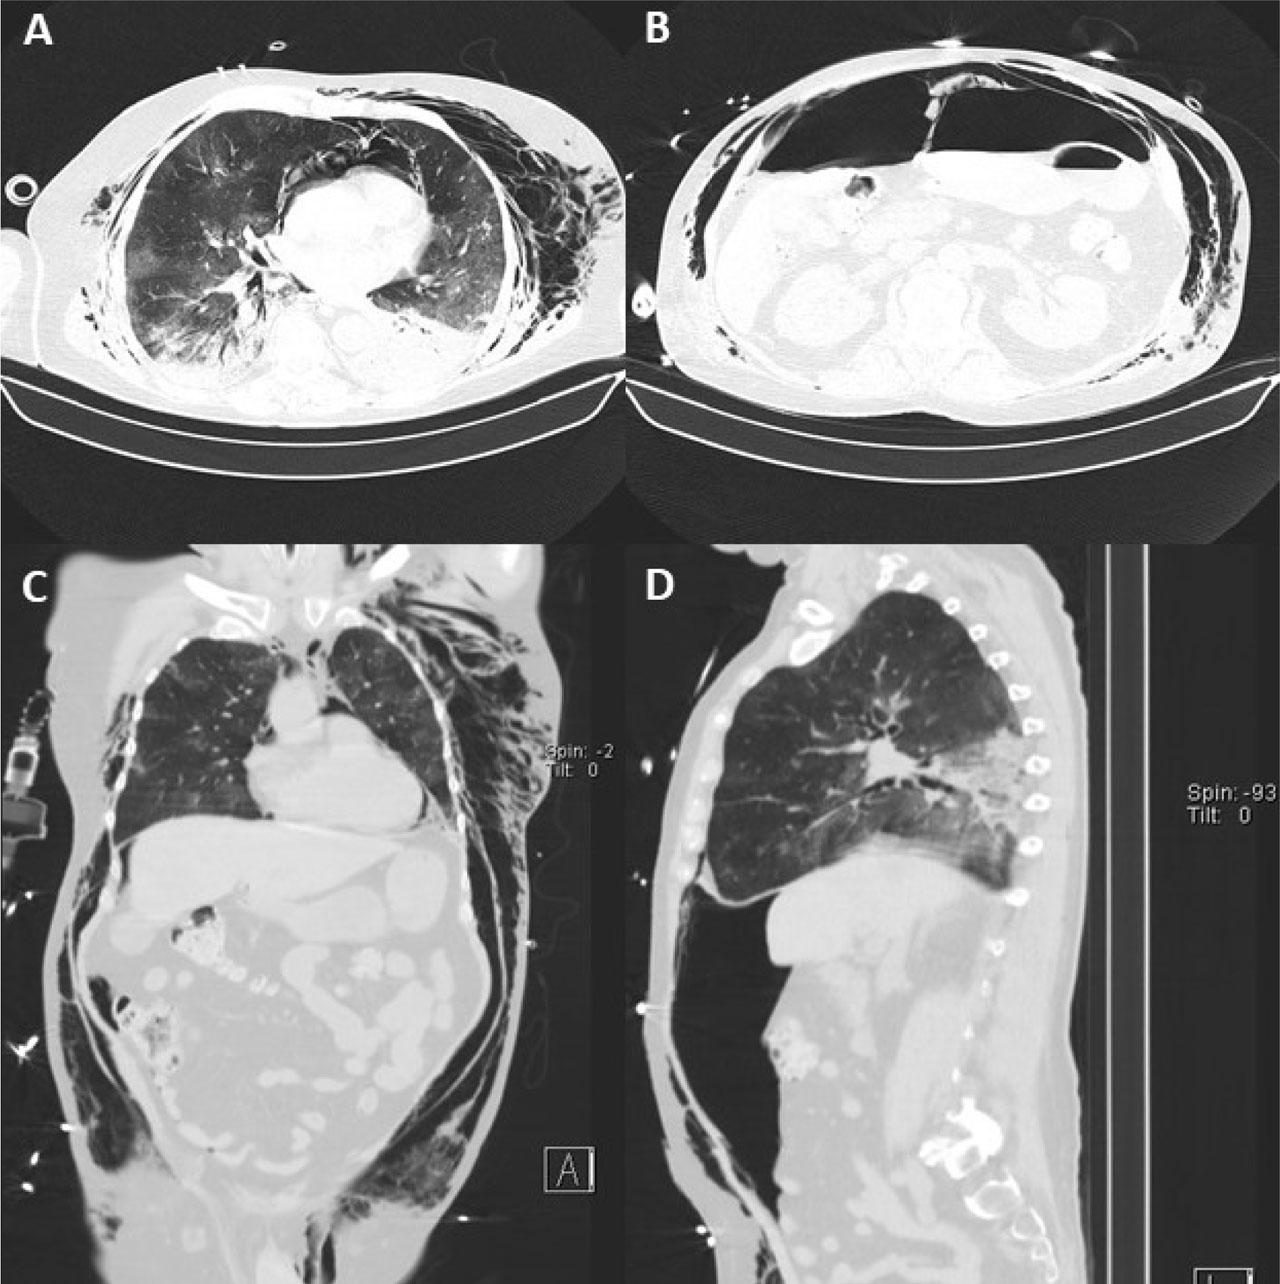

Fig. 2.